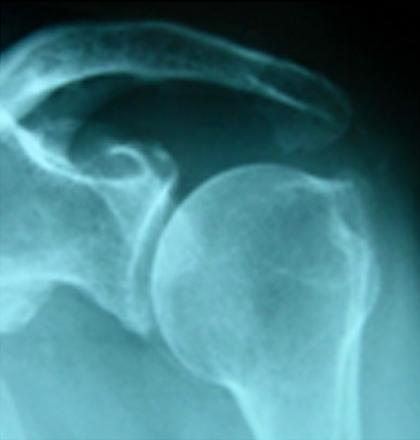

ตัวอย่างการผ่าตัดผ่านกล้องรักษากระดูกงอกทับเส้นเอ็นหัวไหล่

เป็นโรคที่พบได้บ่อยในกลุ่มคนวัยทำงาน และผู้สูงอายุ  เกิดจากการเสียดสีอย่างเรื้อรัง ระหว่างเส้นเอ็นหุ้มข้อไหล่ กับปลายกระดูกสะบัก ในขณะที่ยกแขนขึ้นเหนือศีรษะ จึงทำให้เกิดอาการปวดที่ไหล่ เป็นๆ หายๆโดยเฉพาะอย่างยิ่งขณะยกแขนขึ้นสูงหรือกางแขนออก ผลที่ตามมาคือจะมีการเสื่อมสภาพของเส้นเอ็น จนท้ายที่สุดอาจทำให้เส้นเอ็นหุ้มข้อไหล่ขาดได้  เมื่อถึงเวลานั้นจะส่งผลกระทบต่อการใช้ชีวิตประจำวัน และการทำงานอย่างมาก

ช่วงแรกผู้ป่วยจะมีอาการปวดบริเวณไหล่ โดยเฉพาะด้านหน้าและด้านข้างของหัวไหล่ อาจร้าวลงไปถึงข้อศอกได้  อาการปวดจะเป็นมากขึ้นเวลายกแขนขึ้นด้านหน้าและด้านข้าง ส่วนมากจะมีประวัติปวดไหล่เวลากลางคืน และปวดมากเวลานอนตะแคงทับแขนข้างที่มีอาการ ในระยะที่รุนแรงมากจะพบเส้นเอ็นฉีกขาดร่วมด้วย ทำให้แขนอ่อนแรงขณะที่กางไหล่ ยกไหล่ขึ้นได้อย่างลำบาก หรือไม่ได้เลย